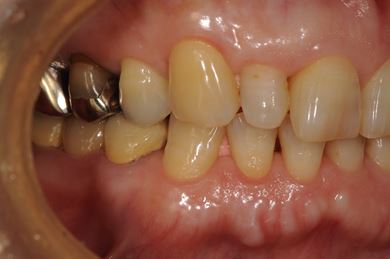

インプラントの症例写真 IMPLANT

骨再生スピードインプラント治療+セラミック治療

| 性別/年齢 | 女性 / 58歳 | ||||||||||||||||||||||||||||||||

| 主訴 | 左上前歯となりがゆらついている。他院でインプラントが必要と言われ、相談に来ました。 | ||||||||||||||||||||||||||||||||

| 治療方針 | 骨再生法によりインプラント治療を可能にする。抜歯と同時にインプラント埋入を行い、治療期間を短縮する。 | ||||||||||||||||||||||||||||||||

| 治療内容 | インプラント3本(抜歯即日スピードインプラント、GBR)、メタルボンドセラミッククラウン1本、ハイブリッドセラミッククラウン4本(ハイブリッドセラミック用土台1本) | ||||||||||||||||||||||||||||||||